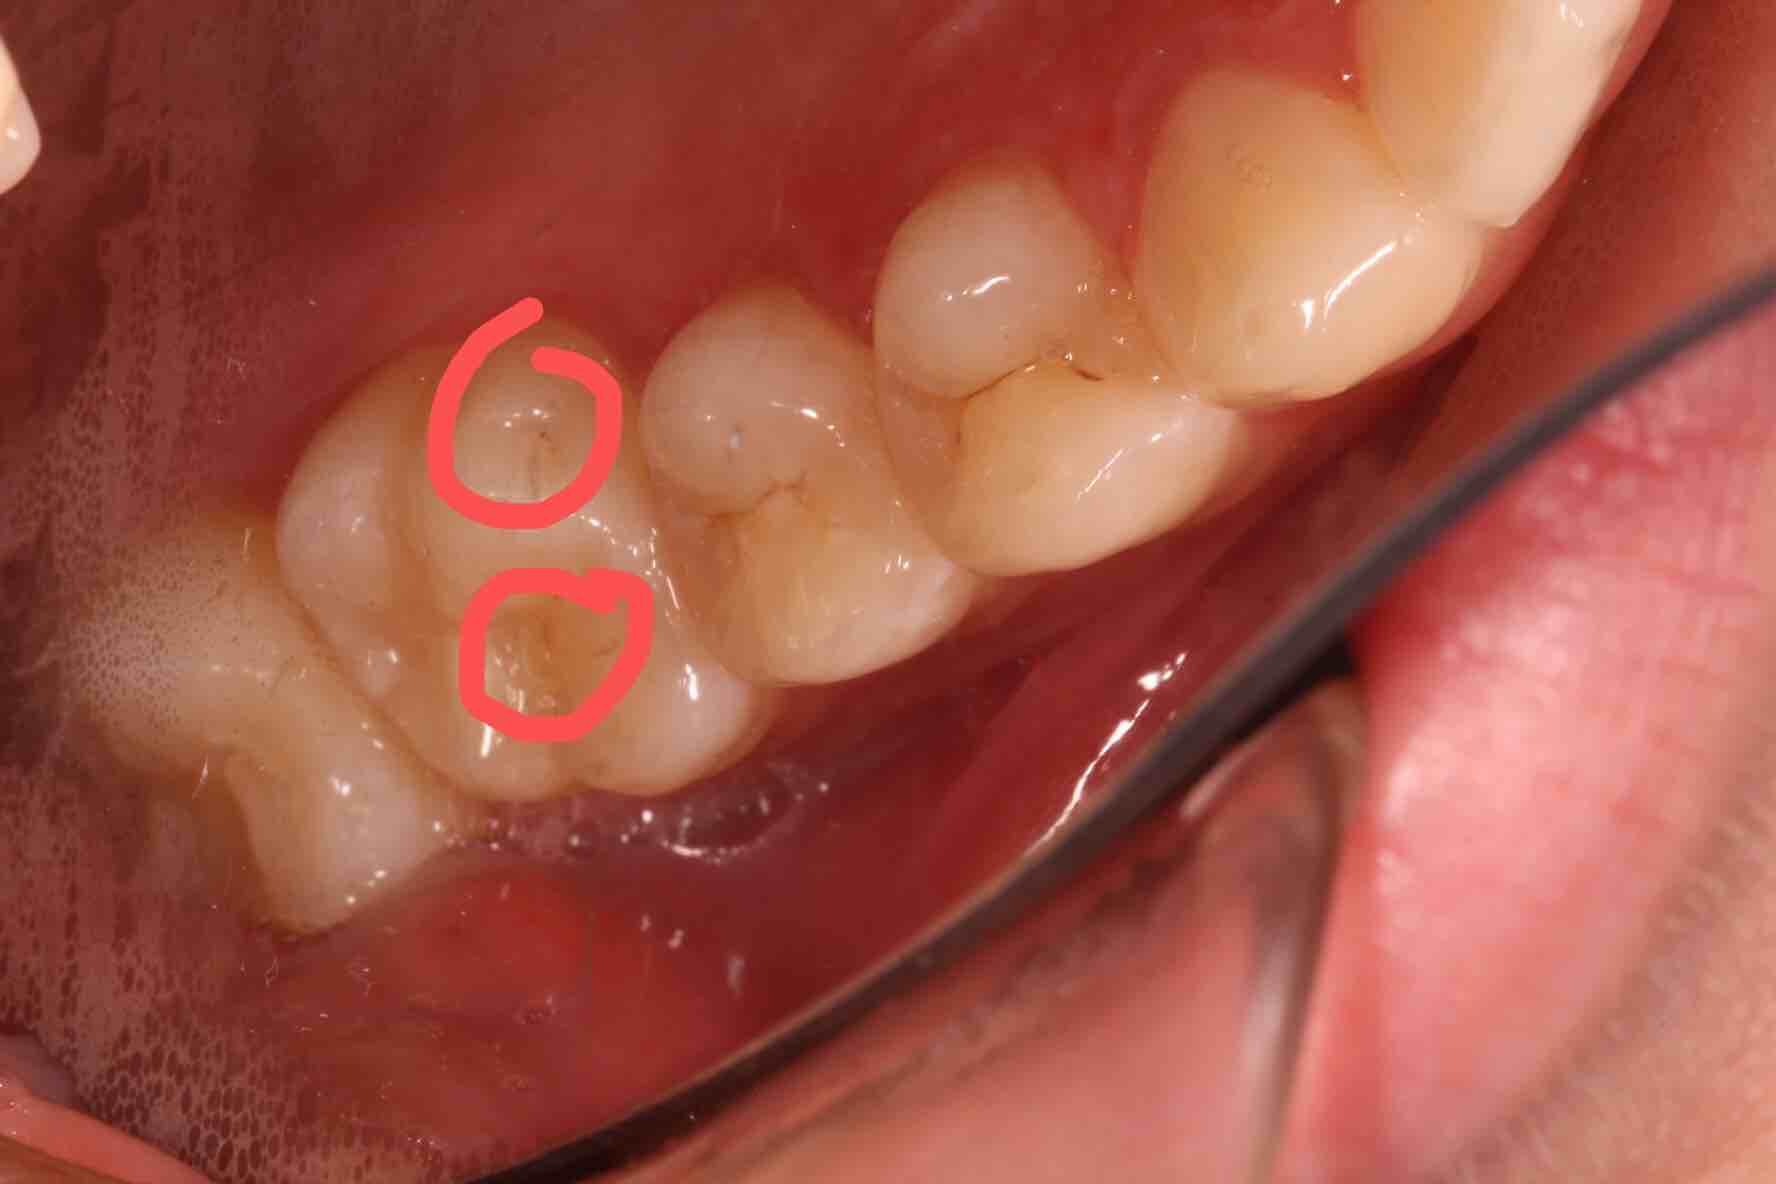

铒激光微创补牙 :这样的窝沟点隙,有点龋坏,用球钻去除,破坏好牙有点多,不忍心;有没有更好的办法呢,用铒激光去除龋坏,专心、专业去除坏牙,还有杀菌、消毒、脱敏的功效,减少补牙术后敏感症状及继发龋坏的发生,另外还有酸蚀的作用,减少了化学药物的影响;没有窝轮机的振动,非常轻柔的啪啪的响声,能够高效、微创去除龋坏,高科技一铒激光微创补牙,您值得拥有!